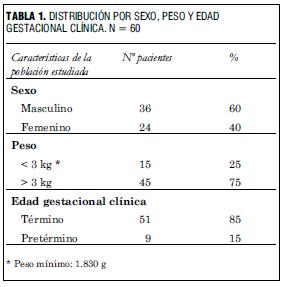

El seguimiento se realizó con un promedio de 5 años y 6 meses (rango de 4 meses a 11 años). La muestra está constituida por 36 varones y 24 niñas, con 85% de nacidos a término y peso al nacer promedio de 3 kilos, con un límite mínimo de peso de 1.830 gramos (tabla 1).

Se efectúa un seguimiento promedio de 5 años y 6 meses (rango 4 meses a 11 años) en un grupo de pacientes con las siguientes características al ingreso: 25% con peso menor de 3 kg (mínimo 1.830 g) y 60% del sexo masculino.